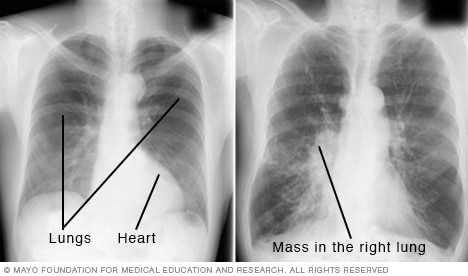

Chest X-ray

A chest X-ray helps detect problems with the heart and lungs. The chest X-ray on the left is typical. The image on the right shows a mass in the right lung.